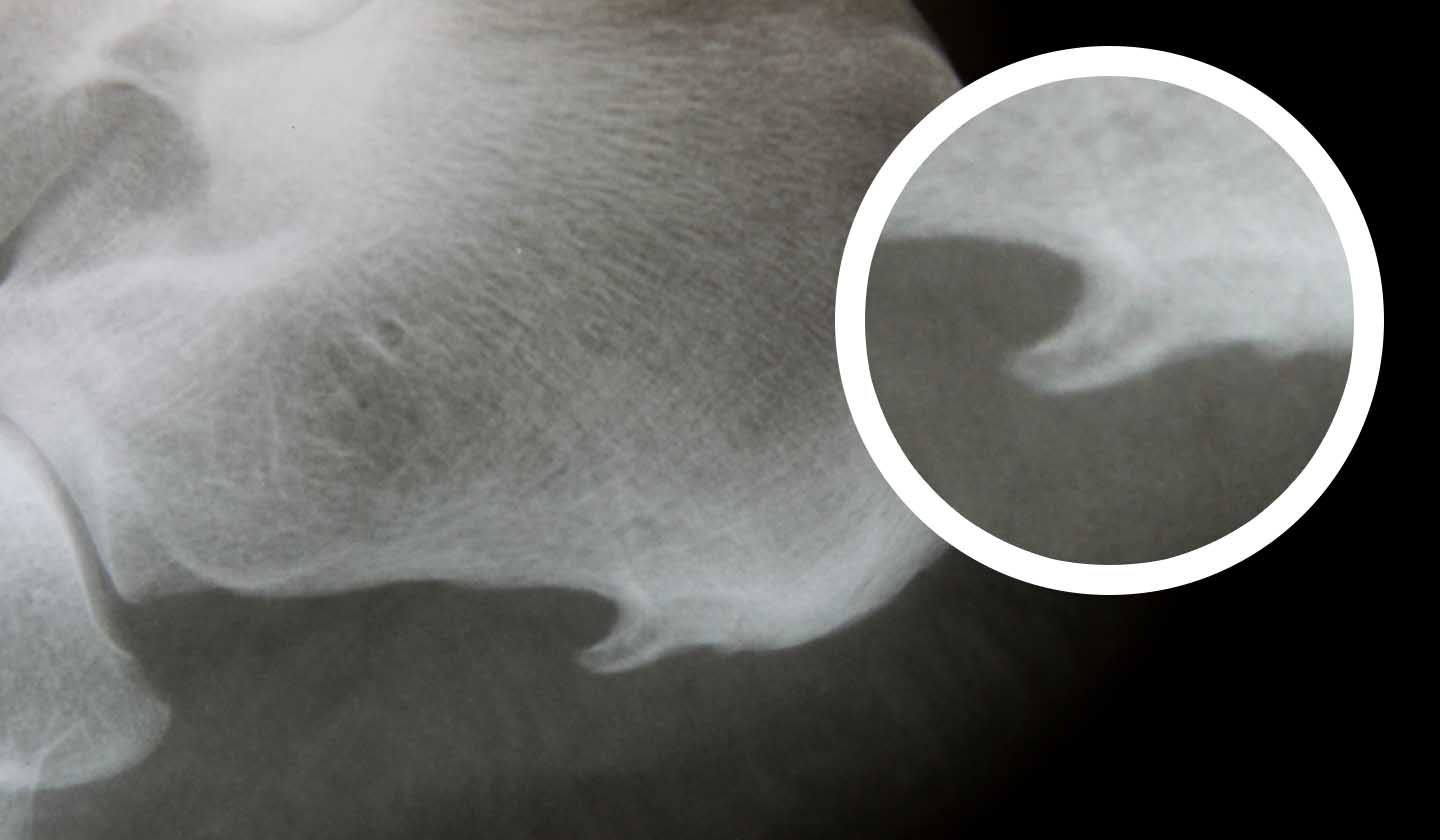

What is a heel spur?

It is a bony protuberance (which reflects an abnormal calcium deposit) that forms at the bottom of the calcaneus (heel bone), next to the insertion of the plantar fascia or in the posterior region of the calcaneus, next to the insertion area of the Achilles tendon.

The diagnosis must be made by a specialist doctor (orthopaedist) who may carry out several tests to make the correct diagnosis (X-ray, Magnetic resonance).